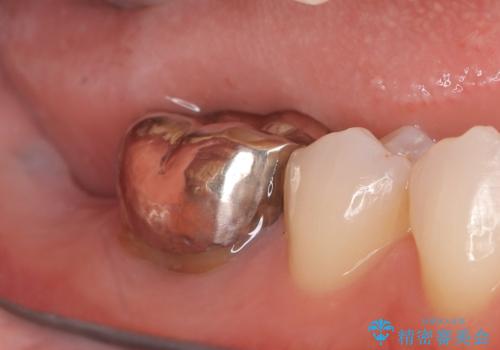

- 患者様は、奥歯を失ったことで「しっかり噛めるようになりたい」とのご希望で来院されました。ブリッジや入れ歯ではなく、インプラントによる治療を希望されたため、精密検査を実施。骨の状態が良好であったため、1回法(1回の手術でインプラント埋入とヒーリングアバットメント装着を同時に行う方法)を選択しました。これにより、外科的負担を軽減しながら、治療期間の短縮も図ることができました。

手術は1回で完了し、局所麻酔下でインプラントを埋入した後、ヒーリングアバットメントを装着。術後の腫れや痛みも少なく、患者様はスムーズに日常生活へ戻ることができました。約3ヶ月の治癒期間を経て、セラミッククラウンをセット。見た目の美しさはもちろん、天然歯に近い噛み心地を実現しました。患者様からは「違和感なくしっかり噛める」とご満足の声をいただきました。